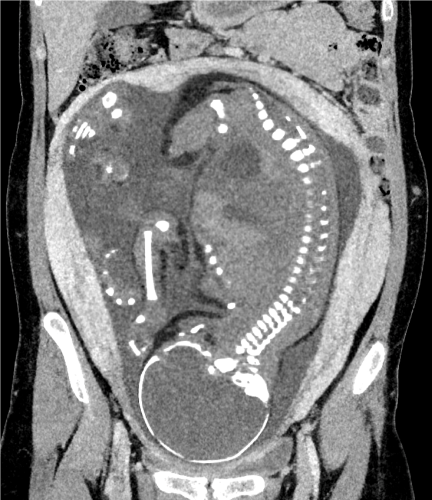

The deep learning reconstruction method (DLR) we first developed is a technique that uses deep learning models trained with low-noise target images to generate high-quality images with reduced noise. As shown in Figure 1, it is now possible to obtain high-quality images by applying a deep learning model to cross-sectional images reconstructed using conventional methods from projection data obtained by CT scanning (2,3). The results shown in Figure 2 confirm that the noise is significantly reduced and higher-quality CT images are obtained compared to images obtained using conventional methods.

Fig. 2: Fetal CT image processed using DLR shows substantial noise reduction compared to the conventional method.